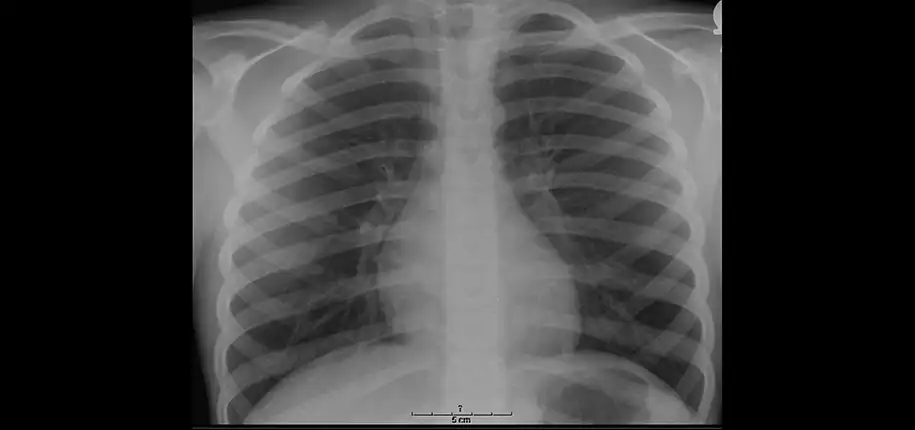

Your child’s healthcare provider may order a chest x-ray for many reasons, including trouble breathing, cough, fever, chest pain, or injury to the chest area. Chest x-rays can identify abnormalities of the lungs, airway, heart, mediastinum (middle chest area), and bones.

Chest x-rays can show infections (such as pneumonia) or a collapsed lung (called a pneumothorax). Chronic lung conditions like asthma and cystic fibrosis can be evaluated with a chest x-ray. Certain cancers can also be identified with chest x-rays.

(Normal chest x-ray, featured image above)